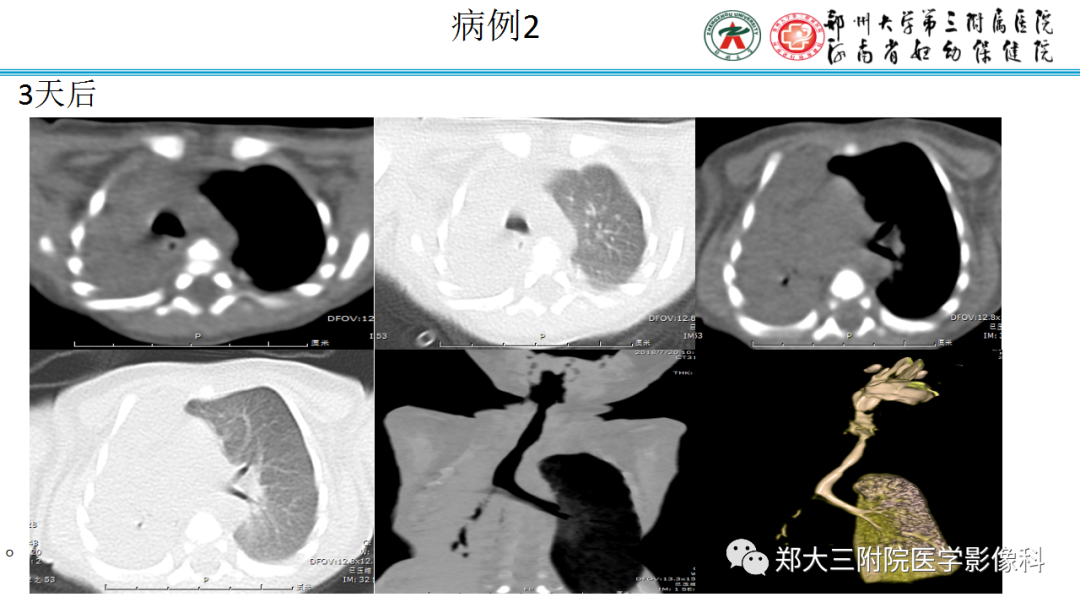

二、肺炎型

2、病灶常有一个主病灶,常位于下肺。后沿气道播散为多发病灶。

3、重力作用,叠瓦征。近叶间裂因重力效应,呈膨隆改变。

4、增强后不均匀强化,存在低强化区呈弱强化或无强化,因此可见“血管造影征。”血管毛糙与肺炎有统计学差异。

5、支气管粗细不均,呈“枯树枝征”,但与肺炎这一点鉴别不具有统计学差异。可发生支气管扩张

6、空腔形成,部分蜂窝状改变。

7、孤立斑片型少有胸腔积液,多发斑片型常有。

9.粘液腺癌的变化规律:结节缓慢发展而来,向周围播散形成斑片后可快速进展,有时支气管镜后或粘液排出后局部可形成好转的假象。病灶可沿肺泡和支气管播散。

三、本例是一个误诊多年的病例,给我们很多启示:

1.多学科探讨的重要性:肾内科忽视肺部病变,后续需要呼吸、影像、病理共同探讨。

2.粘液腺癌易伪装成肺炎的形态,尤其是当患者本身具有免疫色彩的时候,易误诊为间质性肺炎,或肺部感染。若治疗无效,取得病理很重要。

3.粘液腺癌常常因为标本不够,病理无法诊断,影像诊断很重要,取病理方案很重要。甚至多次取病理。

4.回到本例,左下肺病变两次好转,均未经过肿瘤治疗,第一次是支气管镜后,第二次是当其他病变都在进展的情况下,左下肺病变范围反而缩小趋于浅淡。